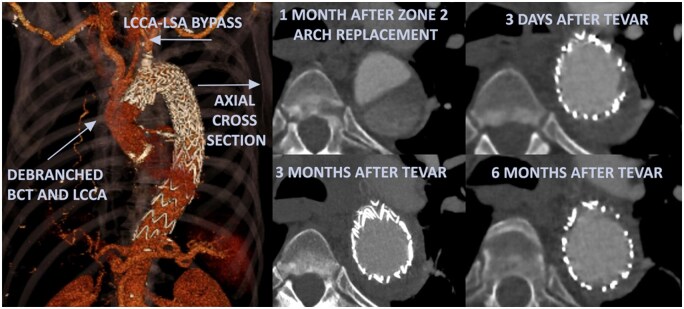

Objectives: This study evaluates a staged selective hybrid approach for acute type A aortic dissection. The approach involves a zone 2 aortic arch replacement with debranching of the brachiocephalic trunk and left common carotid artery to create a landing zone for thoracic endovascular aortic repair. This repair is performed either pre-emptively in the subacute phase to promote remodelling or electively in the chronic phase to manage aneurysm formation.

Results: Of the 91 patients treated for acute type A aortic dissection, 25 underwent zone 2 arch replacement. No perioperative stroke or mortality occurred in this group (mean age 62.7 years, 52% male). Eleven patients (44%) underwent thoracic endovascular aortic repair during follow-up (median interval 152 days, range 38-574). Seven repairs were performed within 6 months of the initial operation. All procedures were technically successful without complications. Early imaging showed stable or reduced aortic diameters in all thoracic endovascular aortic repair patients. In the 14 patients managed conservatively, no relevant aortic growth was observed.

Conclusions: Zone 2 aortic arch replacement with debranching in acute type A aortic dissection can be performed safely. Selective pre-emptive thoracic endovascular aortic repair promoted favourable remodelling, potentially reducing the need for complex, open surgical reinterventions.